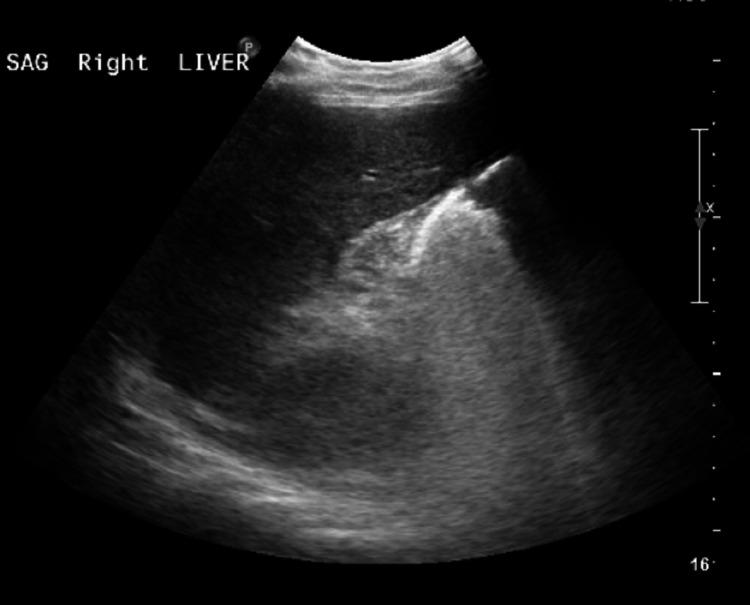

Sickle cell intrahepatic cholestasis (SCIC) is a rare but potentially fatal complication of sickle cell disease (SCD), with high mortality, observed mainly in patients with homozygous sickle cell anemia. Herein, we have reported a case of severe SCIC with a poor outcome despite aggressive measures including exchange transfusion and use of vasopressors. The patient was admitted with generalized weakness, confusion, rigors, chills, and signs of hepatic failure, such as hyperbilirubinemia, hypoalbuminemia, and coagulopathy. There was no evidence of viral hepatitis or biliary obstruction. The patient received two exchange transfusions, but he continued to deteriorate clinically despite exchange transfusion and developed hemorrhagic shock and multiorgan failure. The patient was made comfort care as per family wishes. This case emphasizes the importance of early diagnosis of sickle cell intrahepatic cholestasis and poor prognosis despite aggressive measures.

镰状细胞性肝内胆汁淤积症(SCIC)是镰状细胞病(SCD)一种罕见但可能致命的并发症,死亡率高,主要见于纯合子镰状细胞贫血患者。在此,我们报告了一例严重的SCIC病例,尽管采取了包括换血输血和使用血管加压药在内的积极措施,但预后仍很差。该患者因全身无力、意识模糊、寒战、发冷以及肝功能衰竭迹象(如高胆红素血症、低白蛋白血症和凝血障碍)入院。没有病毒性肝炎或胆道梗阻的证据。患者接受了两次换血输血,但尽管进行了换血输血,他的临床状况仍持续恶化,并发了失血性休克和多器官功能衰竭。根据家属意愿,对患者进行了舒适护理。该病例强调了早期诊断镰状细胞性肝内胆汁淤积症的重要性,以及尽管采取积极措施但预后仍不佳的情况。